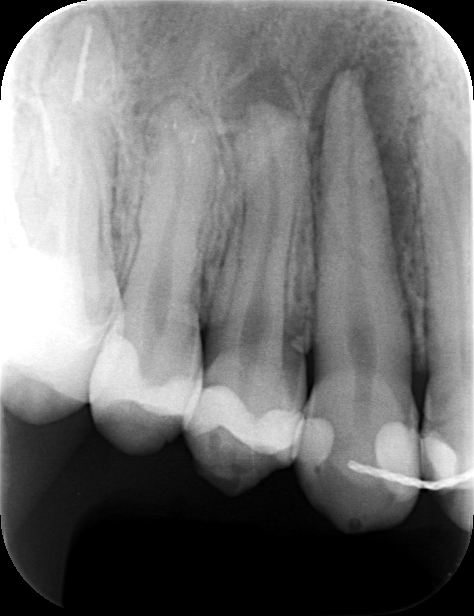

初診時

他院で根管治療を受けていたものの、腫れが引かず、CTの結果「大きな嚢胞があるため抜歯が必要」と診断されていました。

患者様は「できるだけ自分の歯を残したい」との思いで、セカンドオピニオンとして当院を受診されました。